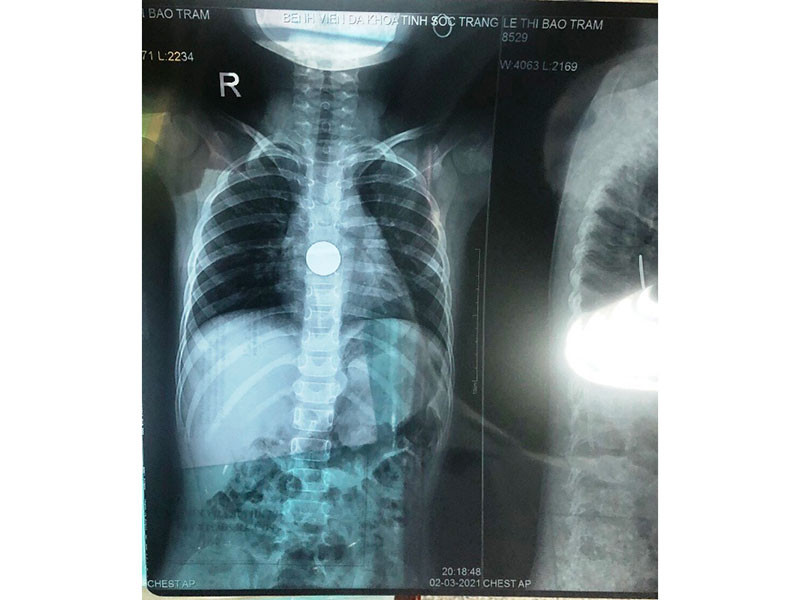

Hình ảnh dị vật đồng xu khi bé T mới nhập viện.

Đến khoảng 21 giờ cùng ngày, Bé T được chuyển đến Khoa Tai Mũi Họng, sau khi cấp cứu ban đầu, sức khỏe tạm ổn. Qua hình ảnh X-Quang, dị vật được xác định là đồng xu đang kẹt ở vị trí cách cung hàm trên 25-26cm, rất gần với dạ dày.